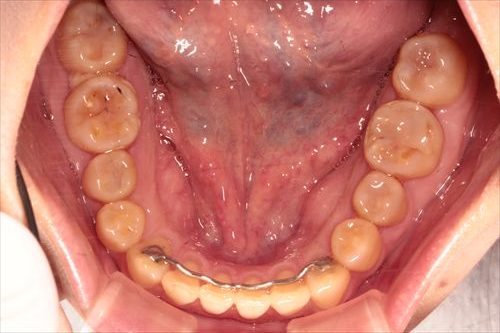

しかし、歯並びがガタガタになることによって上下の前歯のかぶさりがなくなり、ギリギリした時に奥歯しか当たらなくなっています。

その為奥歯はカチカチ咬んでもギリギリ咬んでも歯が当たるため、負担過剰、人間でいえば働きすぎの過労死になることにより、神経が死んだり、割れたり、ぐらつきがでて、抜歯せざるを得なくなってきます。

下の前歯は後戻りが最も起こりやすいので、ワイヤーで止めました。